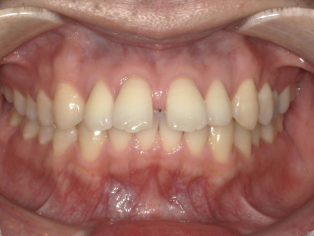

Before Photo

Before